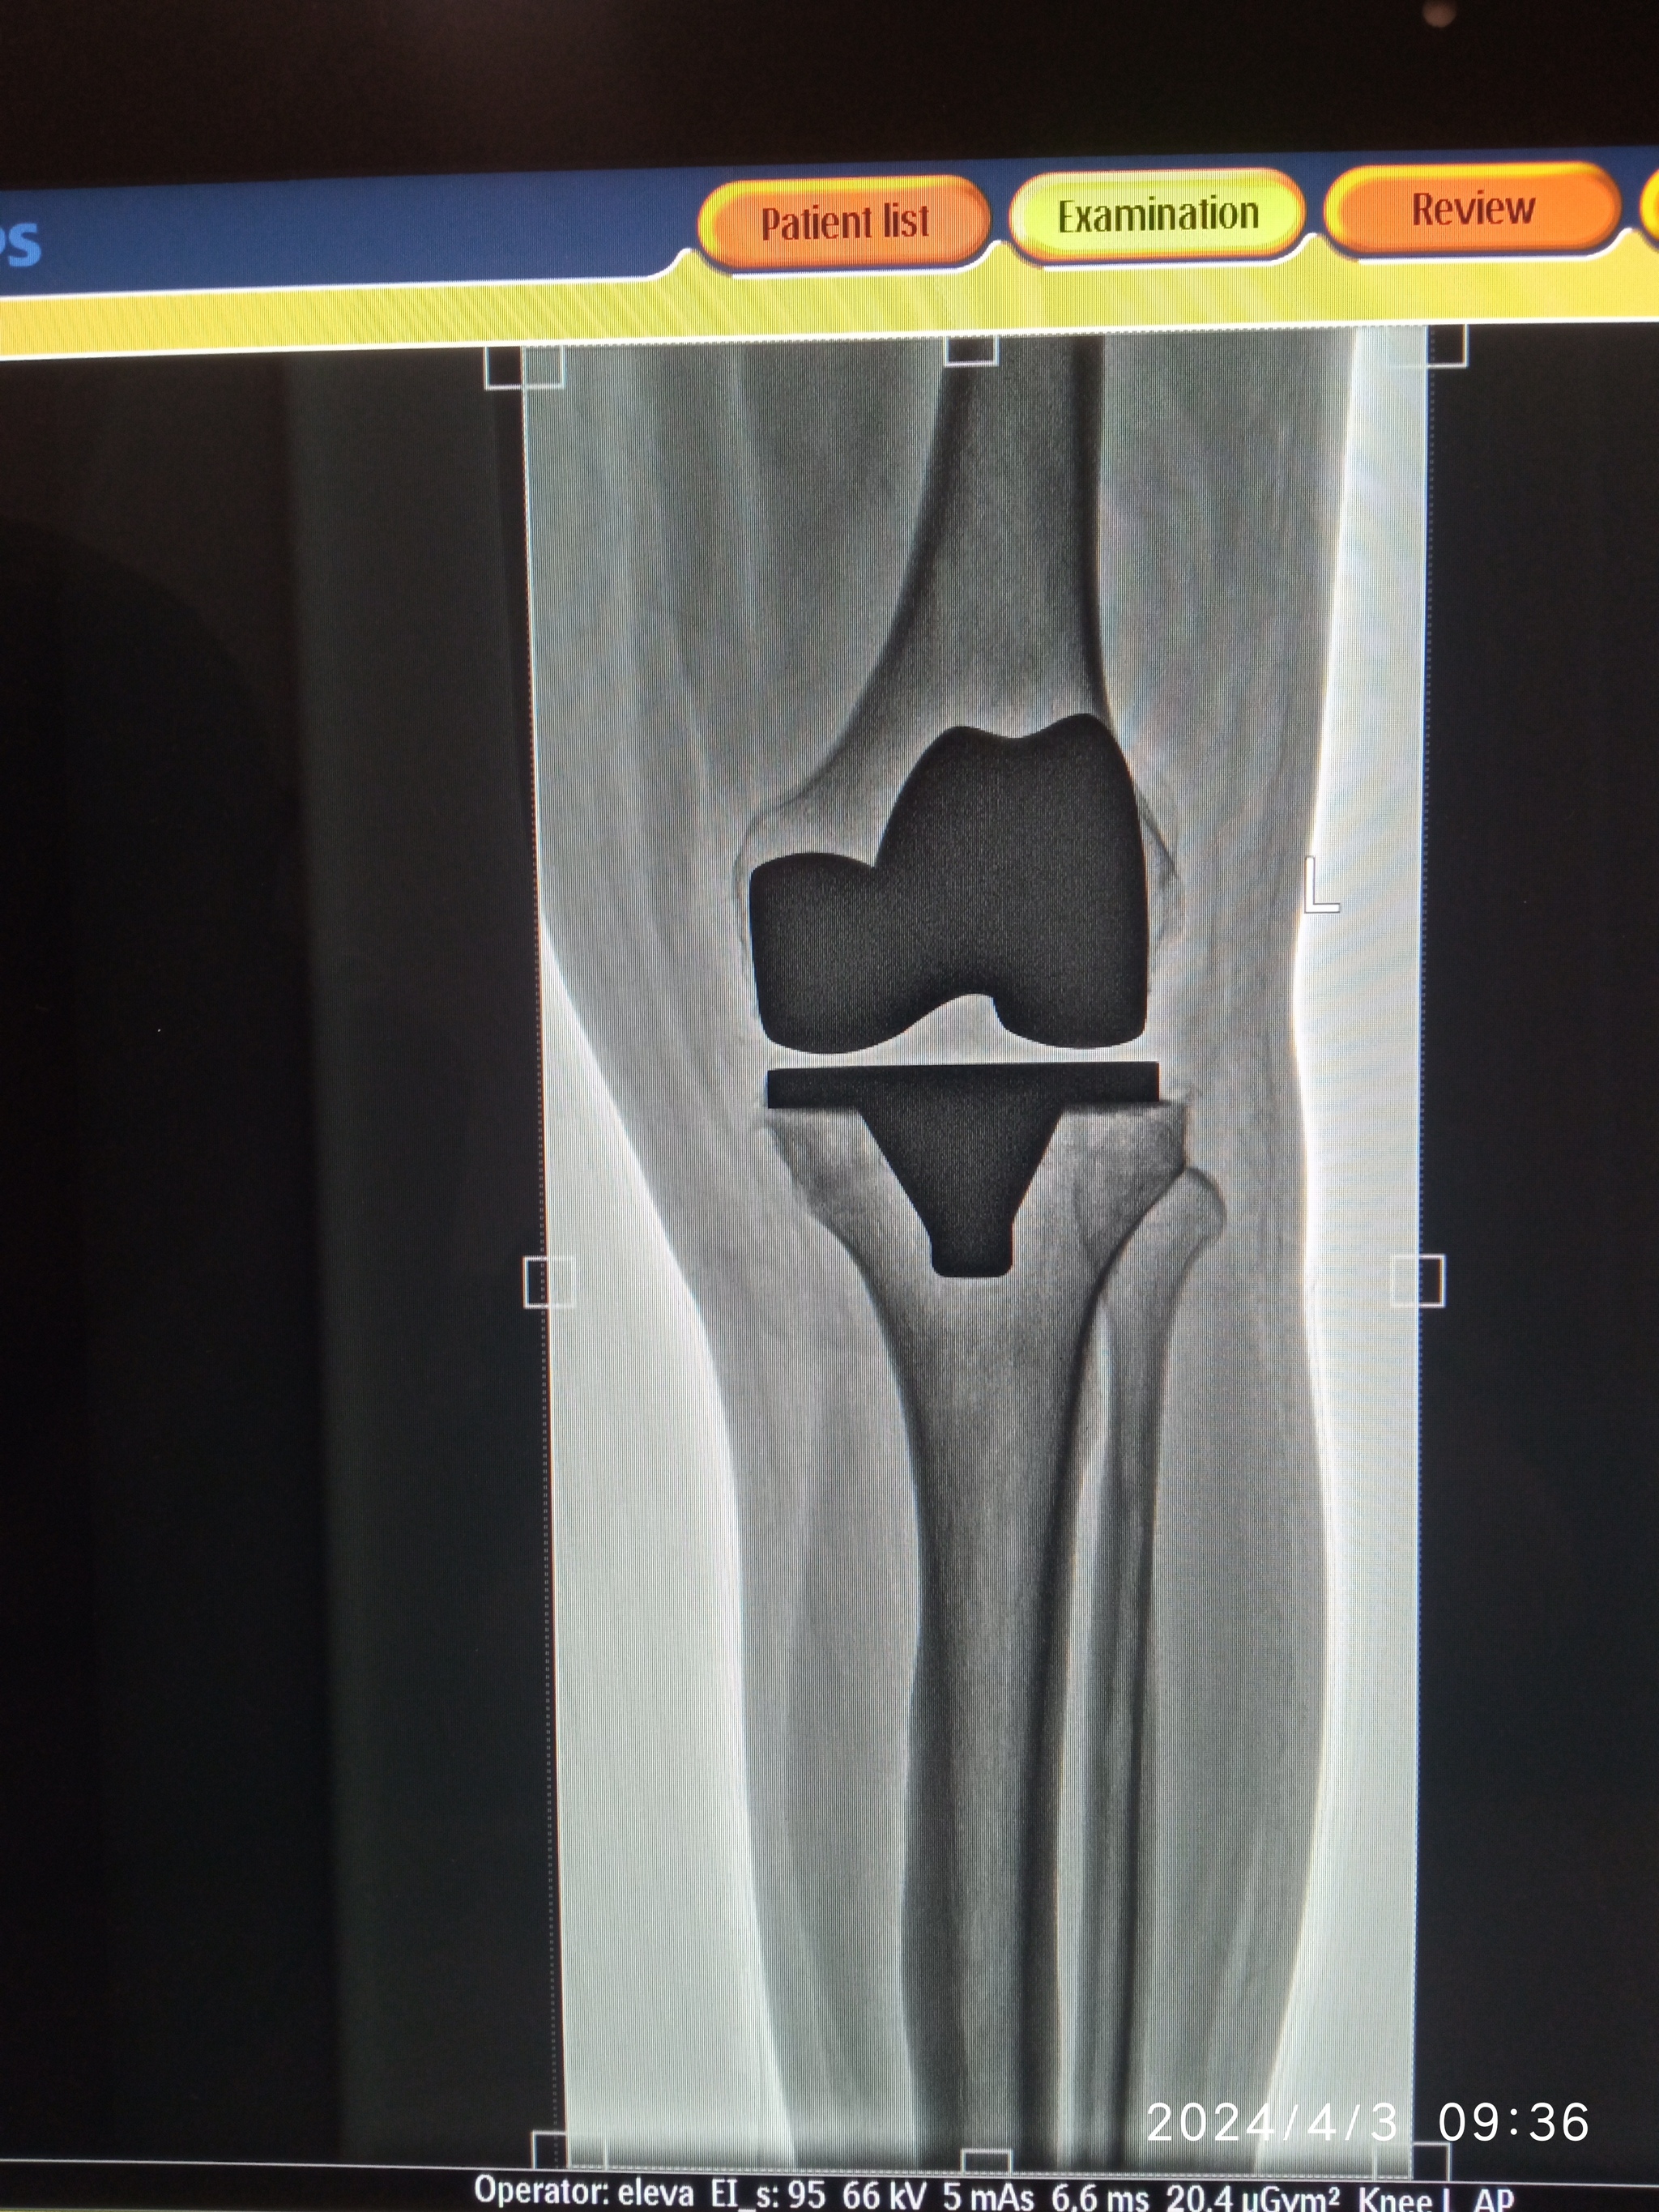

О, а расскажите подробнее? Тоже предстоит протезирование колена в следующем году. Где делали? Сколько вам лет? Как операция и реабилитация? Сейчас как?

Понял, спасибо. А что случилось с коленом что пришлось протезировать? Просто у меня итак отекает от долгого стояния и на дальние расстояния я вообще не хожу, гонартроз 4 степени вследствие многочисленных гематом. Операцию планирую делать чтобы в принципе от боли избавится, и хотя бы ходить нормально не хромая. с болевым синдромом как после операции и сейчас?